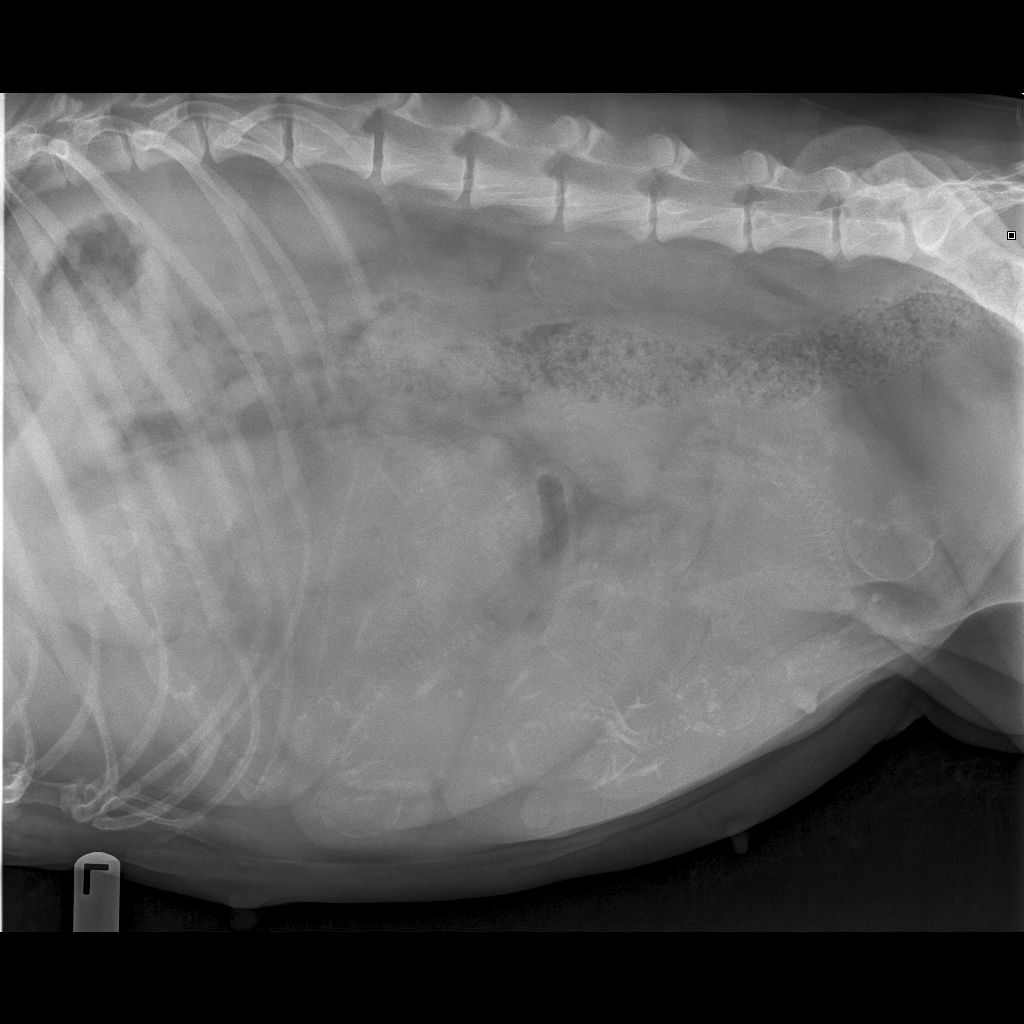

12/30/14 - Xrayed Rio today and she is carrying 11-13 puppies!!! The vet said "too numerous to count"! So excited - a C-section is planned for next Friday or Saturday depending on how she is doing. Would like to wait until Saturday to give the puppies "baking time" but if she starts to go into labor early we will do it Friday. Stay tuned....

1/8/15 - Well Rio is getting pretty uncomfortable - she was up and down all night last night (so I was too!). Still no temperature drop so planning on a C-section Friday or Sat. So anxious to have the little munchkins "on the ground". Scroll down for a picture I took of her a few days ago while laying on the cough.